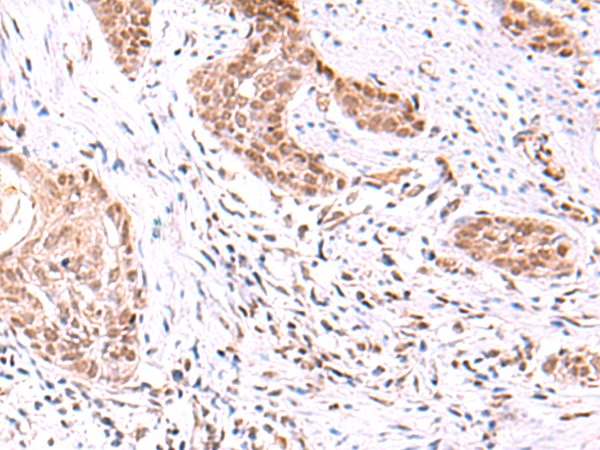

IHC positive control: |

Human lung cancer |